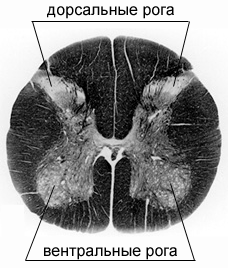

На поперечном срезе спинного мозга (см. ниже) хорошо видно разделение на белое и серое вещество. Белое вещество состоит в основном из аксонов — длинных отростков нейронов, по которым вдоль спинного мозга передаются сигналы. В сером веществе, которое имеет вид бабочки, располагаются сами нейроны, отвечающие за обработку сигналов. В задних «крыльях бабочки» – дорсальных рогах серого вещества спинного мозга – собраны нейроны, которые принимают сигналы от всех частей тела и передают их в мозг. В передних же «крыльях» (вентральных рогах) содержатся двигательные нейроны. Каждый двигательный нейрон соединен с определенной мышцей. Здесь и те мышцы, которыми человек может управлять сознательно, и те, которые сокращаются рефлекторно. Всего в сером веществе спинного мозга порядка 100 тысяч двигательных нейронов.